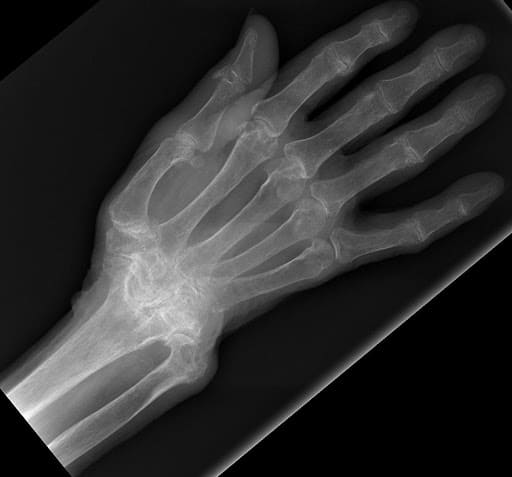

Wrist Fractures

Wrist Scaphoid Fractures

Carpal Injuries

Wrist Scaphoid Nonunion